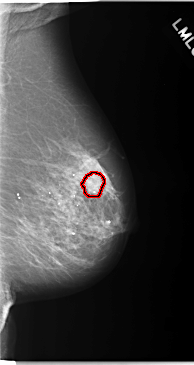

C_0093_1.RIGHT_MLO

LEFT_MLO LINES 5840 PIXELS_PER_LINE 3104 BITS_PER_PIXEL 12 RESOLUTION 50 OVERLAY

FILE: C_0093_1.LEFT_MLO.OVERLAY

TOTAL_ABNORMALITIES 1

ABNORMALITY 1

LESION_TYPE CALCIFICATION TYPE AMORPHOUS DISTRIBUTION CLUSTERED

ASSESSMENT 5

SUBTLETY 4

PATHOLOGY MALIGNANT

TOTAL_OUTLINES 1

BOUNDARY